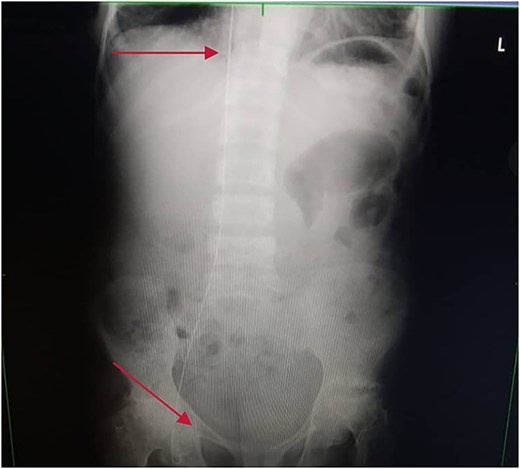

Chest and abdominal X-rays revealed the guide wire extending from the right subclavian vein through the superior vena cava (SVC), right atrium, and inferior vena cava (IVC) to the proximal right femoral vein (Figs 5 and 6).

Chest X-ray showing guide wire extending from the right subclavian vein to the SVC and via the right atrium to the IVC.

Plain abdominal X-ray extending from the IVC through the right iliac vein to the right femoral vein.